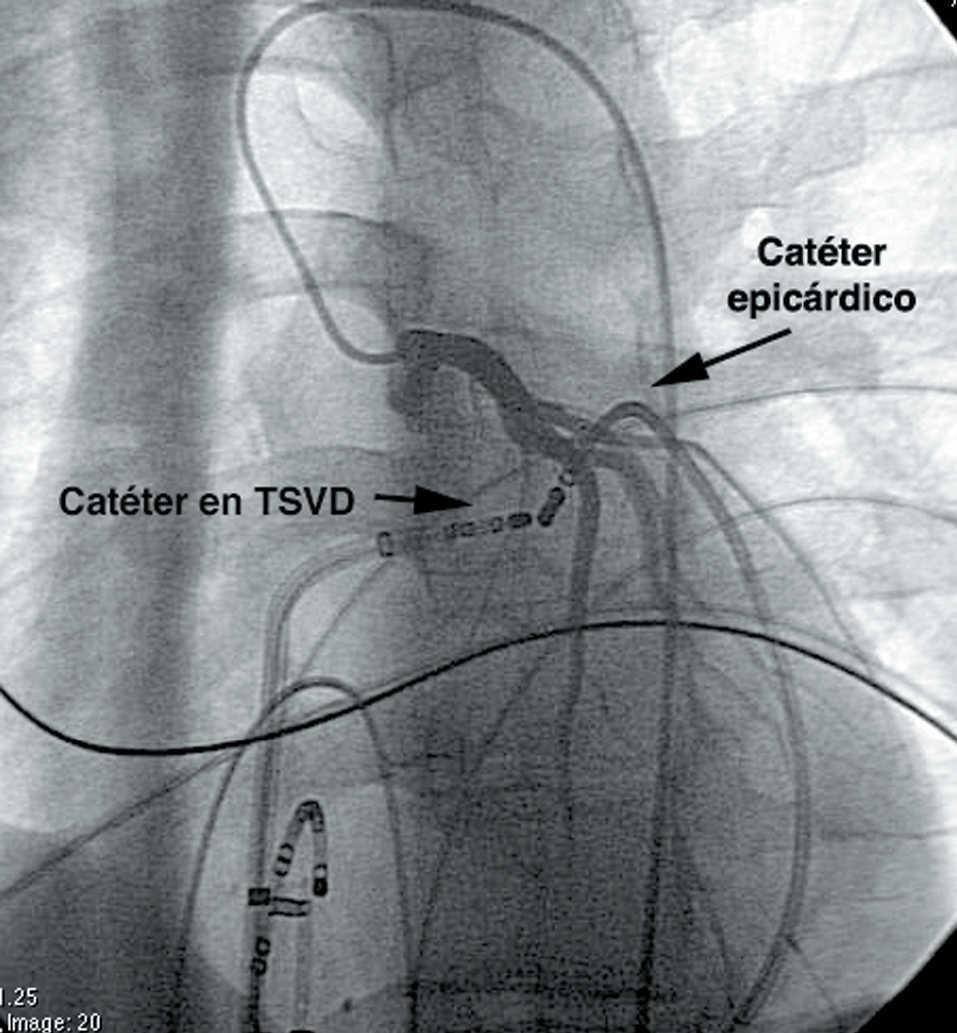

Ablación epicárdica percutánea mediante radiofrecuencia de taquicardias